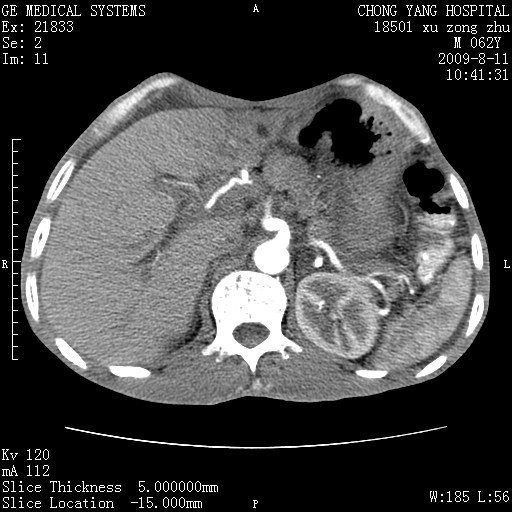

以下是引用杀毒软件在2009-8-11 16:35:00的发言:[br]肝内胆管扩张局限于左叶,胆管内有结石伴肝外胆管结石,胆管壁增厚呈弥漫性并发腹腔积液,胰腺边界模糊。[br][br]考虑---胆总管及肝内胆管结石继发胆管炎及胰腺炎,左肾下极囊肿,腹水。

以下是引用zjzjr在2009-8-11 17:35:00的发言:[br]肝内胆管扩张局限于左叶,胆管内有结石伴肝外胆管结石,胆管壁增厚呈弥漫性并发腹腔积液。[br][br]考虑---胆总管及肝内胆管结石继发胆管炎,左肾下极囊肿,腹水。